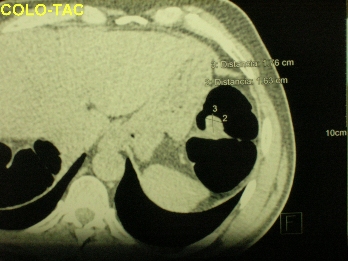

- COLO-TAC: Consiste en el estudio virtual del colon mediante imagen TAC. Está indicado fundamentalmente, al igual que el enema opaco, para estudiar el colon proximal en tumores de colon que no se han podido franquear con el colonoscopio y por lo tanto para descartar pólipos u otro tumor en el resto del colon no explorado. También tienen utilidad para localizar preoperatoriamente el tumor antes de la cirugía laparoscópica.